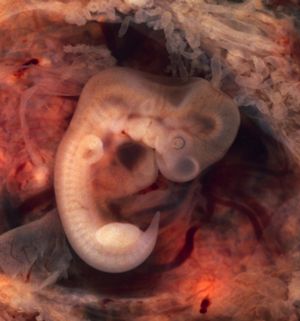

난관 임신은 수정란이 나팔관에 착상할 때 발생한다. 나팔관 내부 표면에 있는 털 모양의 섬모는 수정란을 자궁으로 운반하는 역할을 하는데, 자궁외 임신 후에는 이 섬모의 수가 감소하는 경우가 많아 섬모 손상이 자궁외 임신을 유발할 수 있다는 가설로 이어진다.[22] 흡연 여성은 난관 임신 위험이 더 높은데, 흡연은 섬모 손상 및 파괴의 위험 요인이기 때문이다.[22] 섬모가 손상되면 수정란이 자궁에 도달하는 데 걸리는 시간이 길어진다. 수정란이 제때 자궁에 도달하지 못하면 비부착성 투명대에서 부화하여 나팔관 내벽에 착상하게 되고, 이것이 자궁외 임신으로 이어진다.